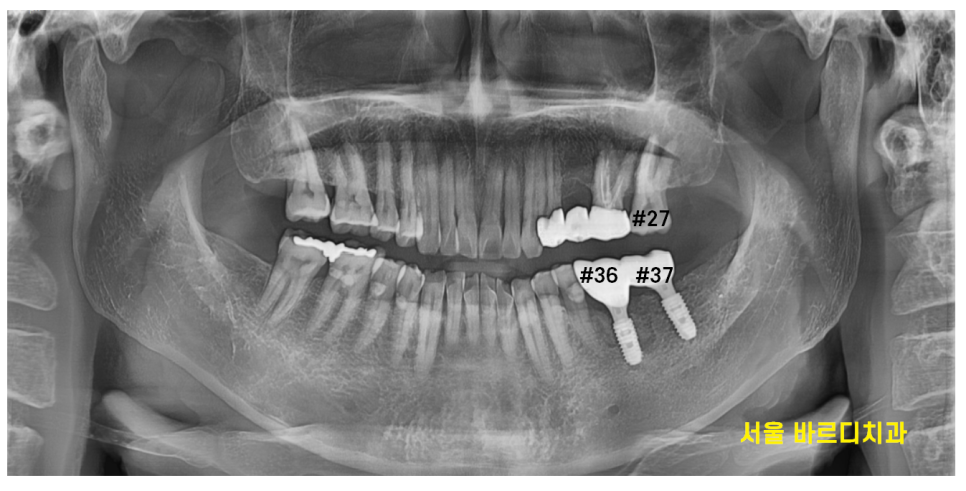

23.12.06

강일동 치과 완성본입니다.

각각 맞물리는 치아가

끝자리가 7번 - 7번으로 끝나죠~?

짝 맞춰서 치료를 끝내드렸습니다.